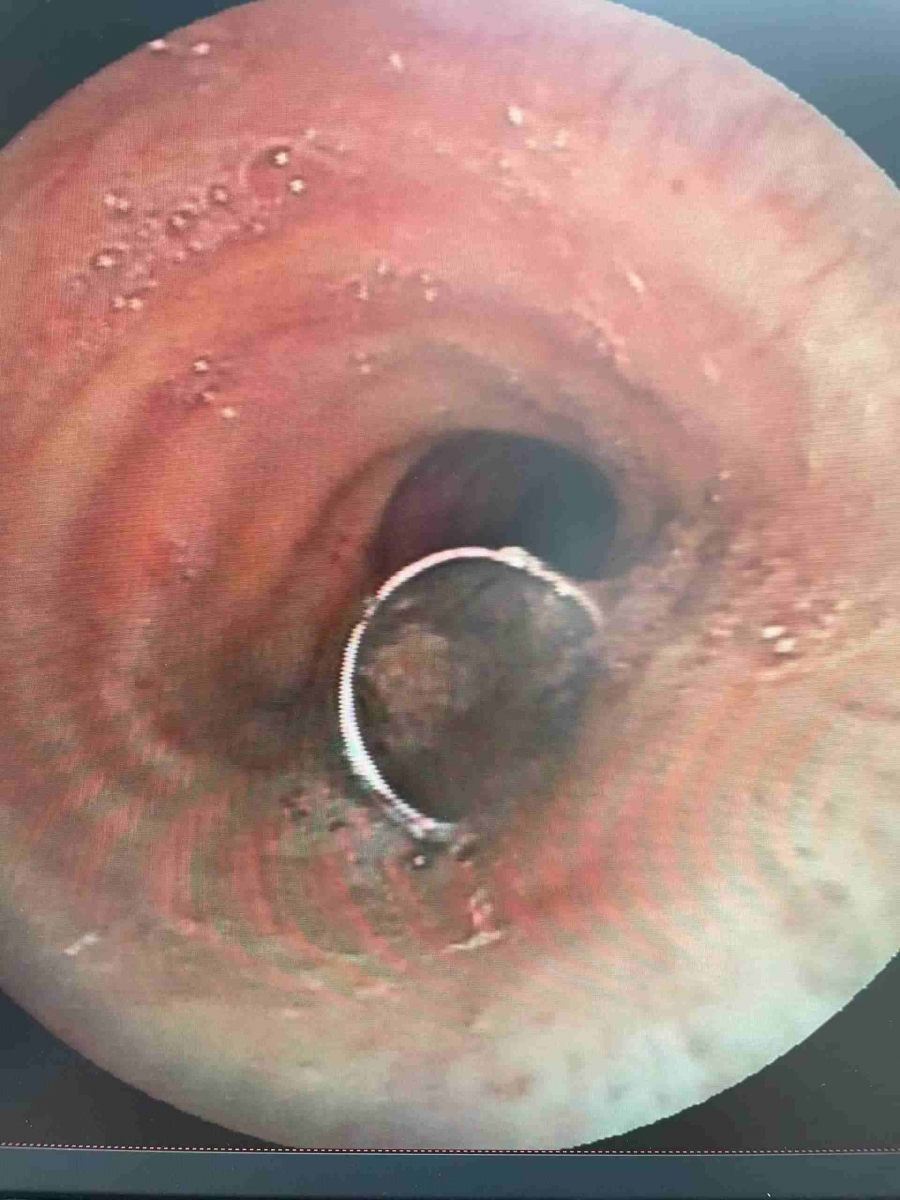

患者柏先生今年73岁,因长期留置气切套管,此次突发呼吸困难,被养老院工作人员发现气管套管脱落至气管内。当天早上8时40分,南溪山医院急诊科迅速联系呼吸与危重症医学科二病区预留床位,并将患者紧急转至病区救治。入院后,吴娟主任医师、李海斌副主任医师联合内镜中心团队立即开展床边支气管镜探查。在多次尝试以异物钳夹取异物未果、异物无法通过声门的情况下,呼吸二病区团队迅速启动应急预案,联系麻醉科团队,改为急诊硬质支气管镜手术取出异物。术中,异物随硬镜一同被顺利取出,从插入硬镜到取出异物仅用时数分钟。12时30分,手术顺利结束,患者安全病房。术后,患者咳嗽、气喘等症状明显改善,充分体现了南溪山医院呼吸与危重症医学科高效的急诊救治能力。

呼吸二病区屈东明主任指出,气道内异物是呼吸科常见的急危重症,若处理不及时,可能迅速导致患者窒息,危及生命。南溪山医院开展的硬质支气管镜手术,能够迅速、有效地解决气道异物堵塞问题,为患者争取宝贵的救治时间。